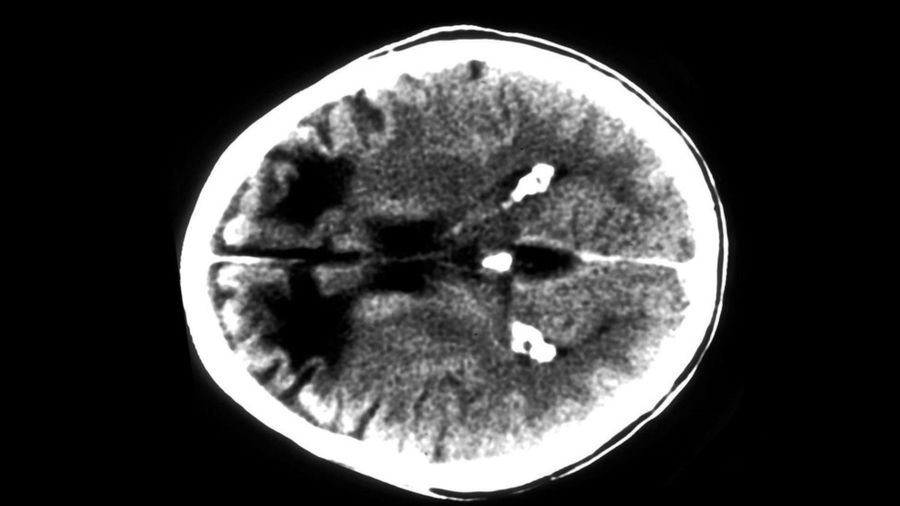

Такая операция предусматривает иссечение нейронных связей (афферентных и эфферентных волокон) между лобными долями и другими отделами мозга.

Во время лоботомии в черепе сверлят отверстия, через которые наносят повреждения в лобных долях коры головного мозга